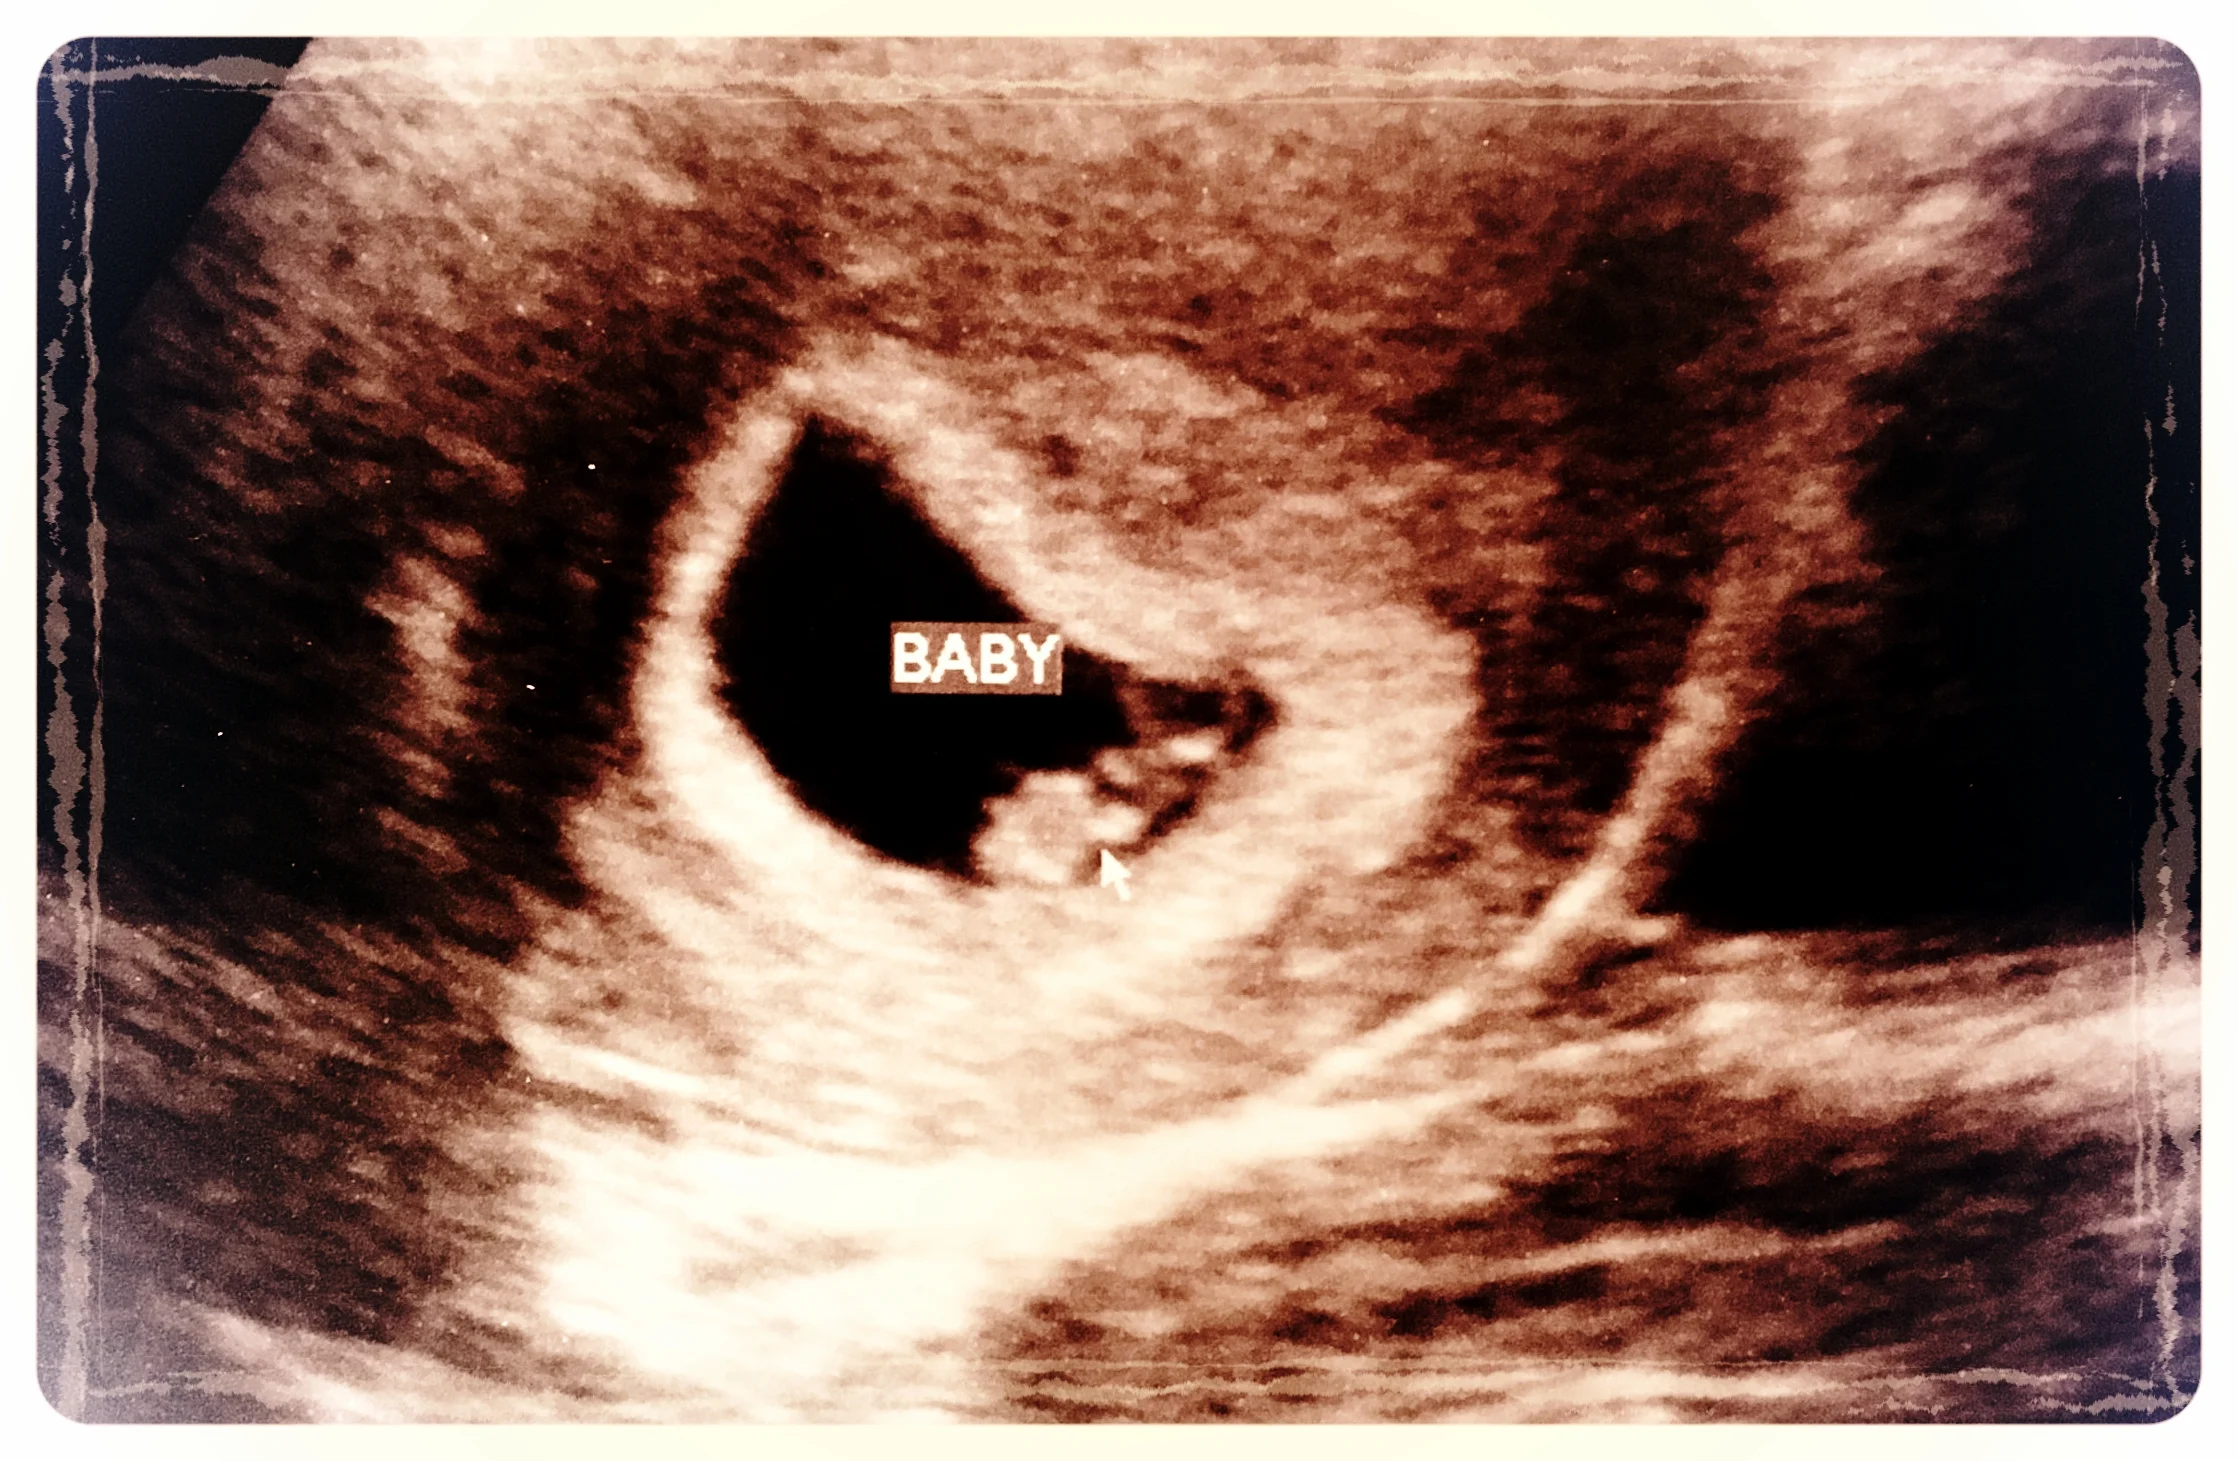

Want to have a real discussion about strong women? Then we have to have a discussion about birth mothers. These women, these WARRIORS, wake up every day with their bellies growing a little bit larger. These same warriors looked death in the face when they were given the option to abort their baby. These warriors had the courage to say, “No, I will sacrifice myself so that death will not win.”